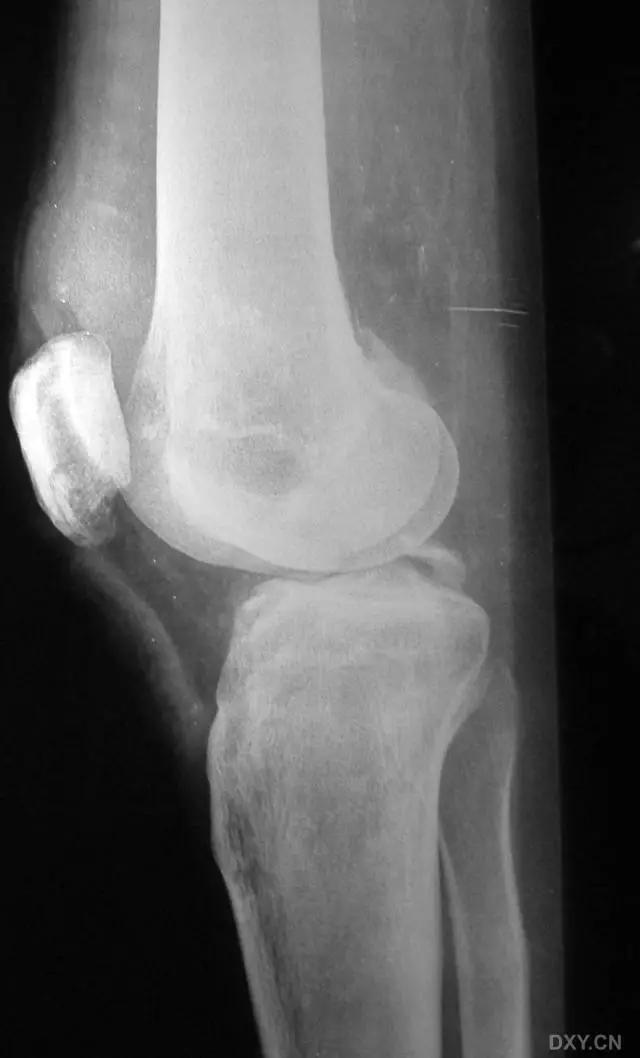

5. Hoffa 骨折

指股骨远端冠状面的骨折。

病例 1:一般股骨髁间、髁上粉碎骨折中含 Hoffa 骨折的不少见,但单纯后髁骨折则很少见。

正位片

侧位片

水平位 CT

第 2 例

第 3 例